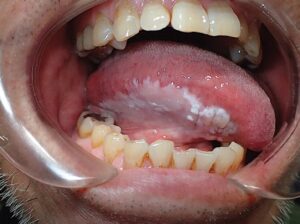

عفونت فک و صورت چیست و چرا باید آن را جدی بگیریم؟

این عفونت‌ها وقتی پیش می‌آیند که چرک در بافت‌های نرم، مثل پوست و عضله‌های صورت، یا حتی استخون فک جمع می‌شود، اما چرا این موضوع انقدر مهم است؟

پوسیدگی که به ریشه دندان رسیده، لثه‌های ملتهب یا دندان عقل گیر کرده داخل فک، می‌توانند باکتری را به جاهای عمیق‌تر ببرند.

بافت‌های این بخش به یکدیگر وصل هستن و عفونت می‌توانددر همه جاها و قسمت‌های بدن پخش شود. از ریشه دندان شروع و به گونه برسد، زیر زبان، یا حتی عمق گردن. اگر به راه تنفسی فشار وارد کند یا وارد خون شود، اوضاع بسیار بدتر از پیش از آن می‌شود.